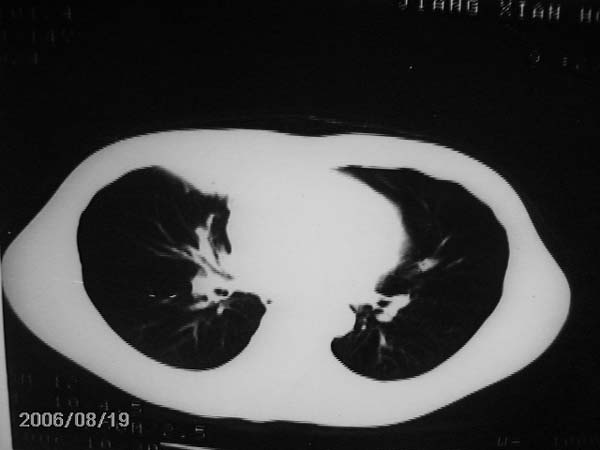

男,13岁,发烧半月,干咳无痰,正规使用抗生素半月,现在仍是午后低烧!!!未做痰检

结合临床考虑:右肺中叶结核可能性大.

右肺中叶结核可能性大

右肺结核,右肺中叶不张

右侧肺门淋巴结好象有增大,会不会是个原发综合症合并感染

右中肺呈大片状密度欠均匀影,内见含气支气管.

结合病史,考虑:右中肺大叶性肺炎(吸收期).

右肺中叶大片状密度增高影,内密度不均匀,右肺门处增大,应该是淋巴结肿大,结合临床首先考虑原发性肺结合可能性大,不排除合并感染可能,建议治疗后复查.